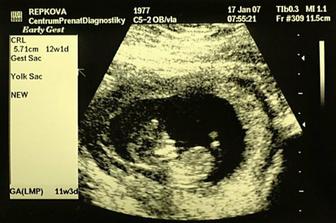

SRPŇÁTKA 2007 - fotky UTZ

album věnované mimískům, které se narodí v srpnu 2007 a jejich maminkám ze "Společného termínu SRPEN"